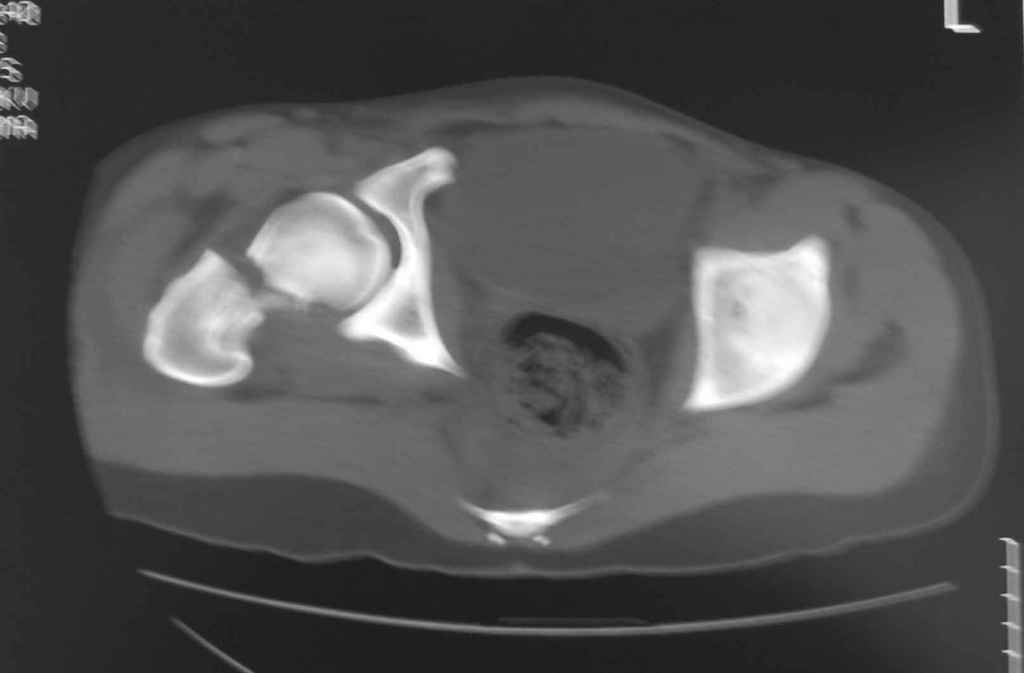

Принципиально важно видеть все срезы КТ через вертлугу, так как тактика лечения будет в первую очередь обусловлена характером перелома ветрлужной впадины, во вторую - вертикальным смещением таза ( где варианты - от банального скелетного вытяжения до ВЧКО или накостного остеосинтеза - в основном зависит от пресловутой "позиции кафедры")

Уважаемый Алексей, на представленных Вами снимках имеется вертикально-нестабильное повреждение тазового кольца без повреждения вертлужной впадины. Учитывая это, а так же растущий возраст ребенка я бы выбрал аппарат внешней фиксации в виде кольцевой опоры, т.к. не смотря на оскольчатый перелом крыла в переднем отделе можно ввести минимум 2 стержня + 1-2 надвертлужно. Этого будет достаточно чтобы "зацепится", выполнить репозицию и дальнейшую фиксацию. Перелом шейки по моему лучше прооперировать 3 канюлированными винтами по АО.